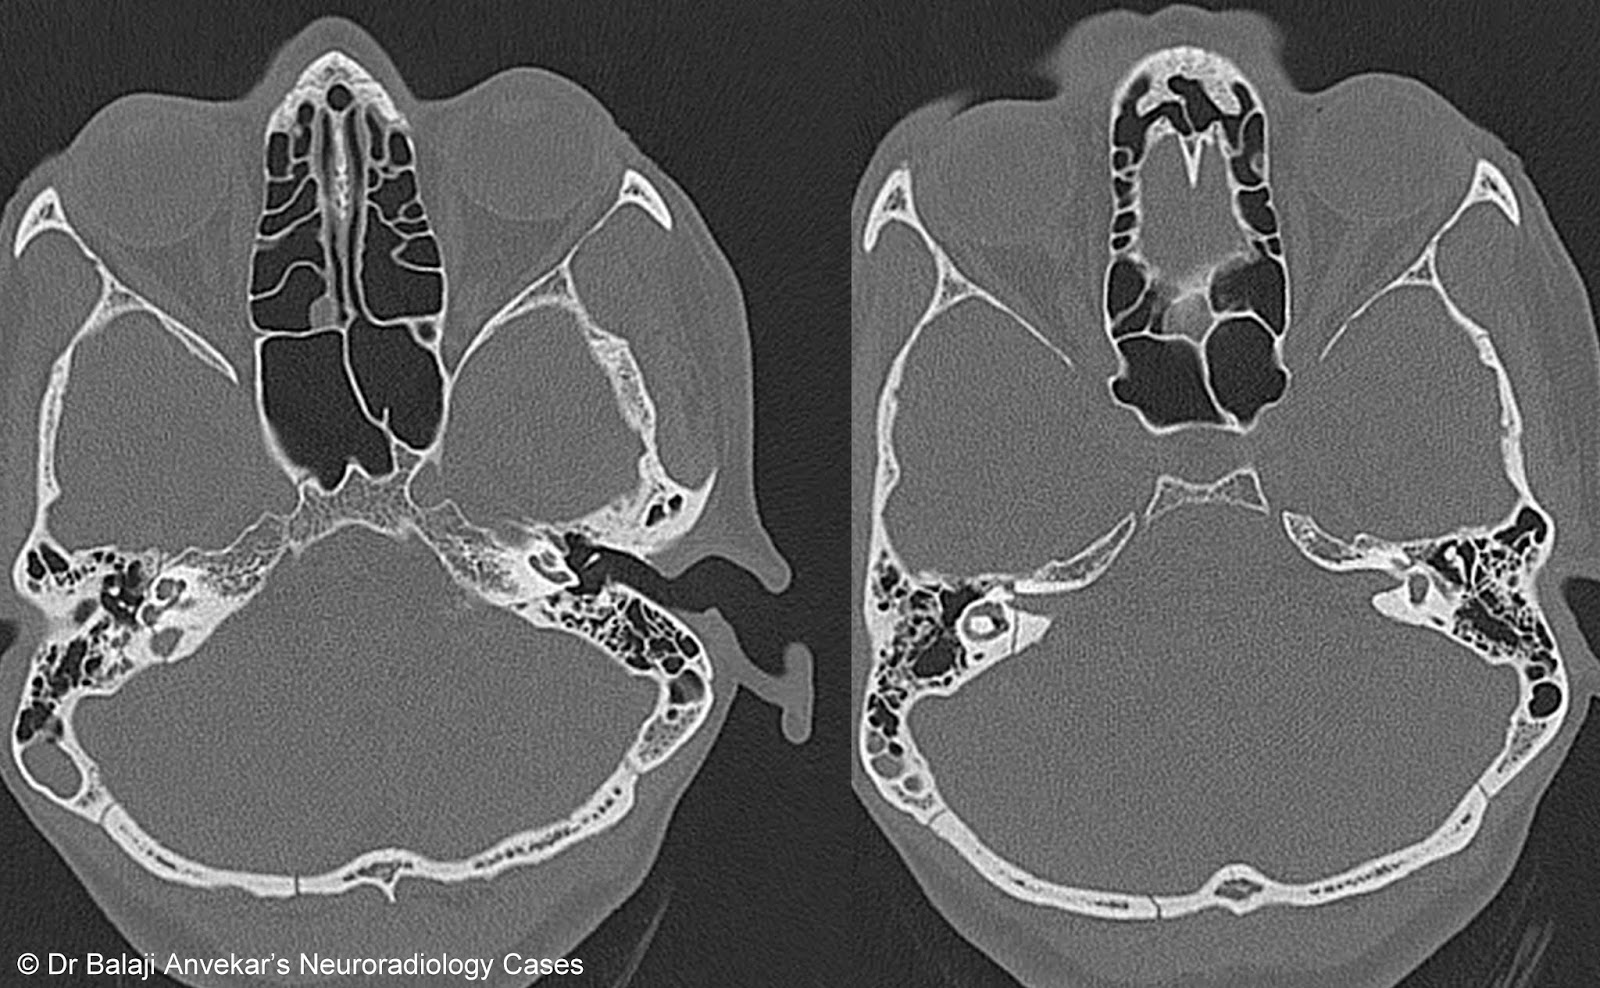

Complex facial fractures

Complex facial fractures 142 photos